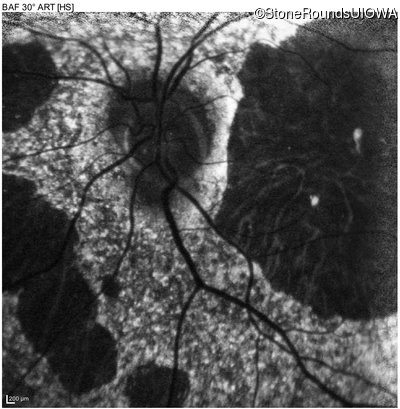

Blue Autofluorescence - Right - 10/200 sc

Exemplar

Blue Autofluorescence - Left - 10/125 -1 sc

Blue Autofluorescence - Left - 10/125 sc